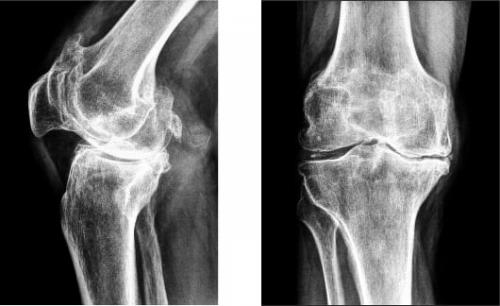

На изображении справа заметно сращение суставной щели.

- гонартроз . Он встречается практически в 50% всех случаев поражения сочленения. Патология развивается очень долго. Среди симптомов этой болезни можно выделить такие: колено не болит в состоянии покоя, однако человеку становится трудно, долго ходить,. Во время движения больной слышит, у него снижается подвижность. Со временем, вследствие изнашивания хряща, расстояние между костными поверхностями уменьшается. При этом появляются, нервы и сосуды сдавливаются, а само колено деформируется;

Гонартроз коленного сустава на рентгене.